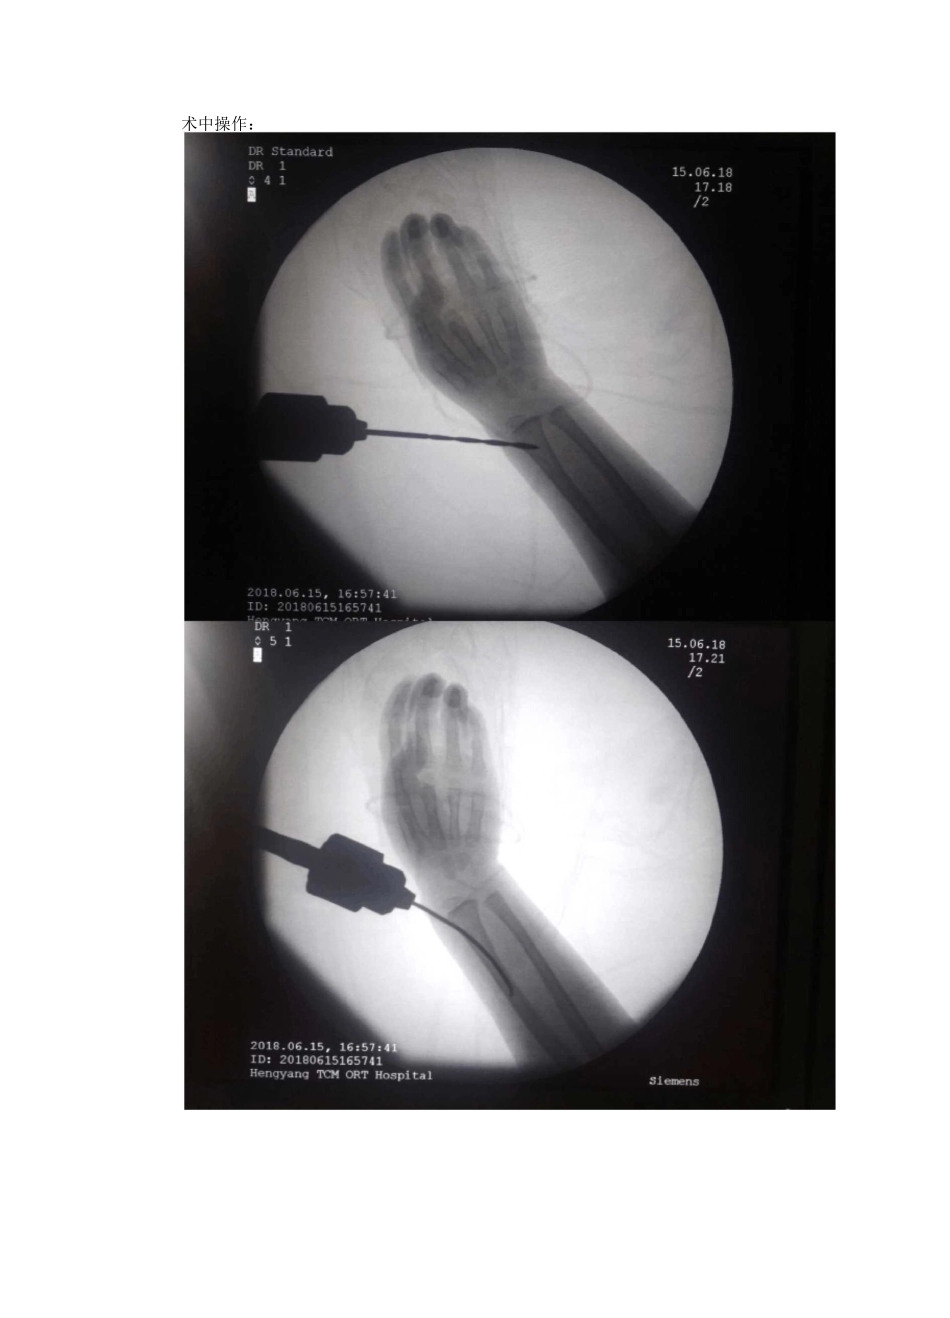

>90%小儿桡骨小头骨折经皮克氏针辅助撬拨复位弹性髓内钉内固定Qc\移位成角3J2.A 橈骨颈骨折分度。依据骨折的移位和成角分度通常来讲成交小于 30 度桡骨颈骨折只需长臂石膏或夹板固定 2-3 周。角度大于 30 度和(或)移位大于 5MM 的桡骨颈骨折,一定要进行骨折复位。患儿杨欣蕾,女,5 岁,因摔伤致右肘关节肿痛办活动受限 1 天于 2018 年 6 月 14 日收住我科。入院 X 线片示:患儿及其父亲诉患儿于 13 日早上 11 时左右在幼儿园不慎摔倒,具体体位着地不详,即感右肘关节持续性疼痛伴肘关节活动受限,余无特殊不适,下午遂在老师陪同下,父母带患儿到南华大学附属一医院就诊,门诊行 X 线片示:“右桡骨小头骨折”建议住院手术治疗,患儿家属不愿手术治疗,后到市其他医院就诊咨询均建议手术治疗,近日为求进一步治疗遂到我院就诊,门诊以“右桡骨小头骨折”收住我科。体查:右肘关节肿胀明显,局部皮肤无破溃,右肘关节外侧局部轻压痛,右肘关节活动受限,前臂旋转活动受限,未扪及明显骨擦感,末梢循环可,右手指即腕关节活动自如,余无特殊。儿童桡骨小头骨折约占肘关节骨折的 5%,其中倾斜移位 60 度以上的桡骨小头骨折患儿约占肘关节骨折的 1%,处理不当常致前臂旋转功能障碍,60 度以上的儿童桡骨小头骨折以往多采用切开复位,克氏针交叉固定,易出现肘关节功能受限、桡骨头缺血性坏死等并发症,而撬拨复位结合弹性髓内针内固定的治疗方法开创了新局面。术中操作:HenqyangTCMORTHospitalQCr201B.06.15,1^7:41IDt20100^15165741HenqyangTCMORTHospitalSiemens术后复位满意,内固定正常:术后外观:术后常规前臂旋后位石膏托外固定。